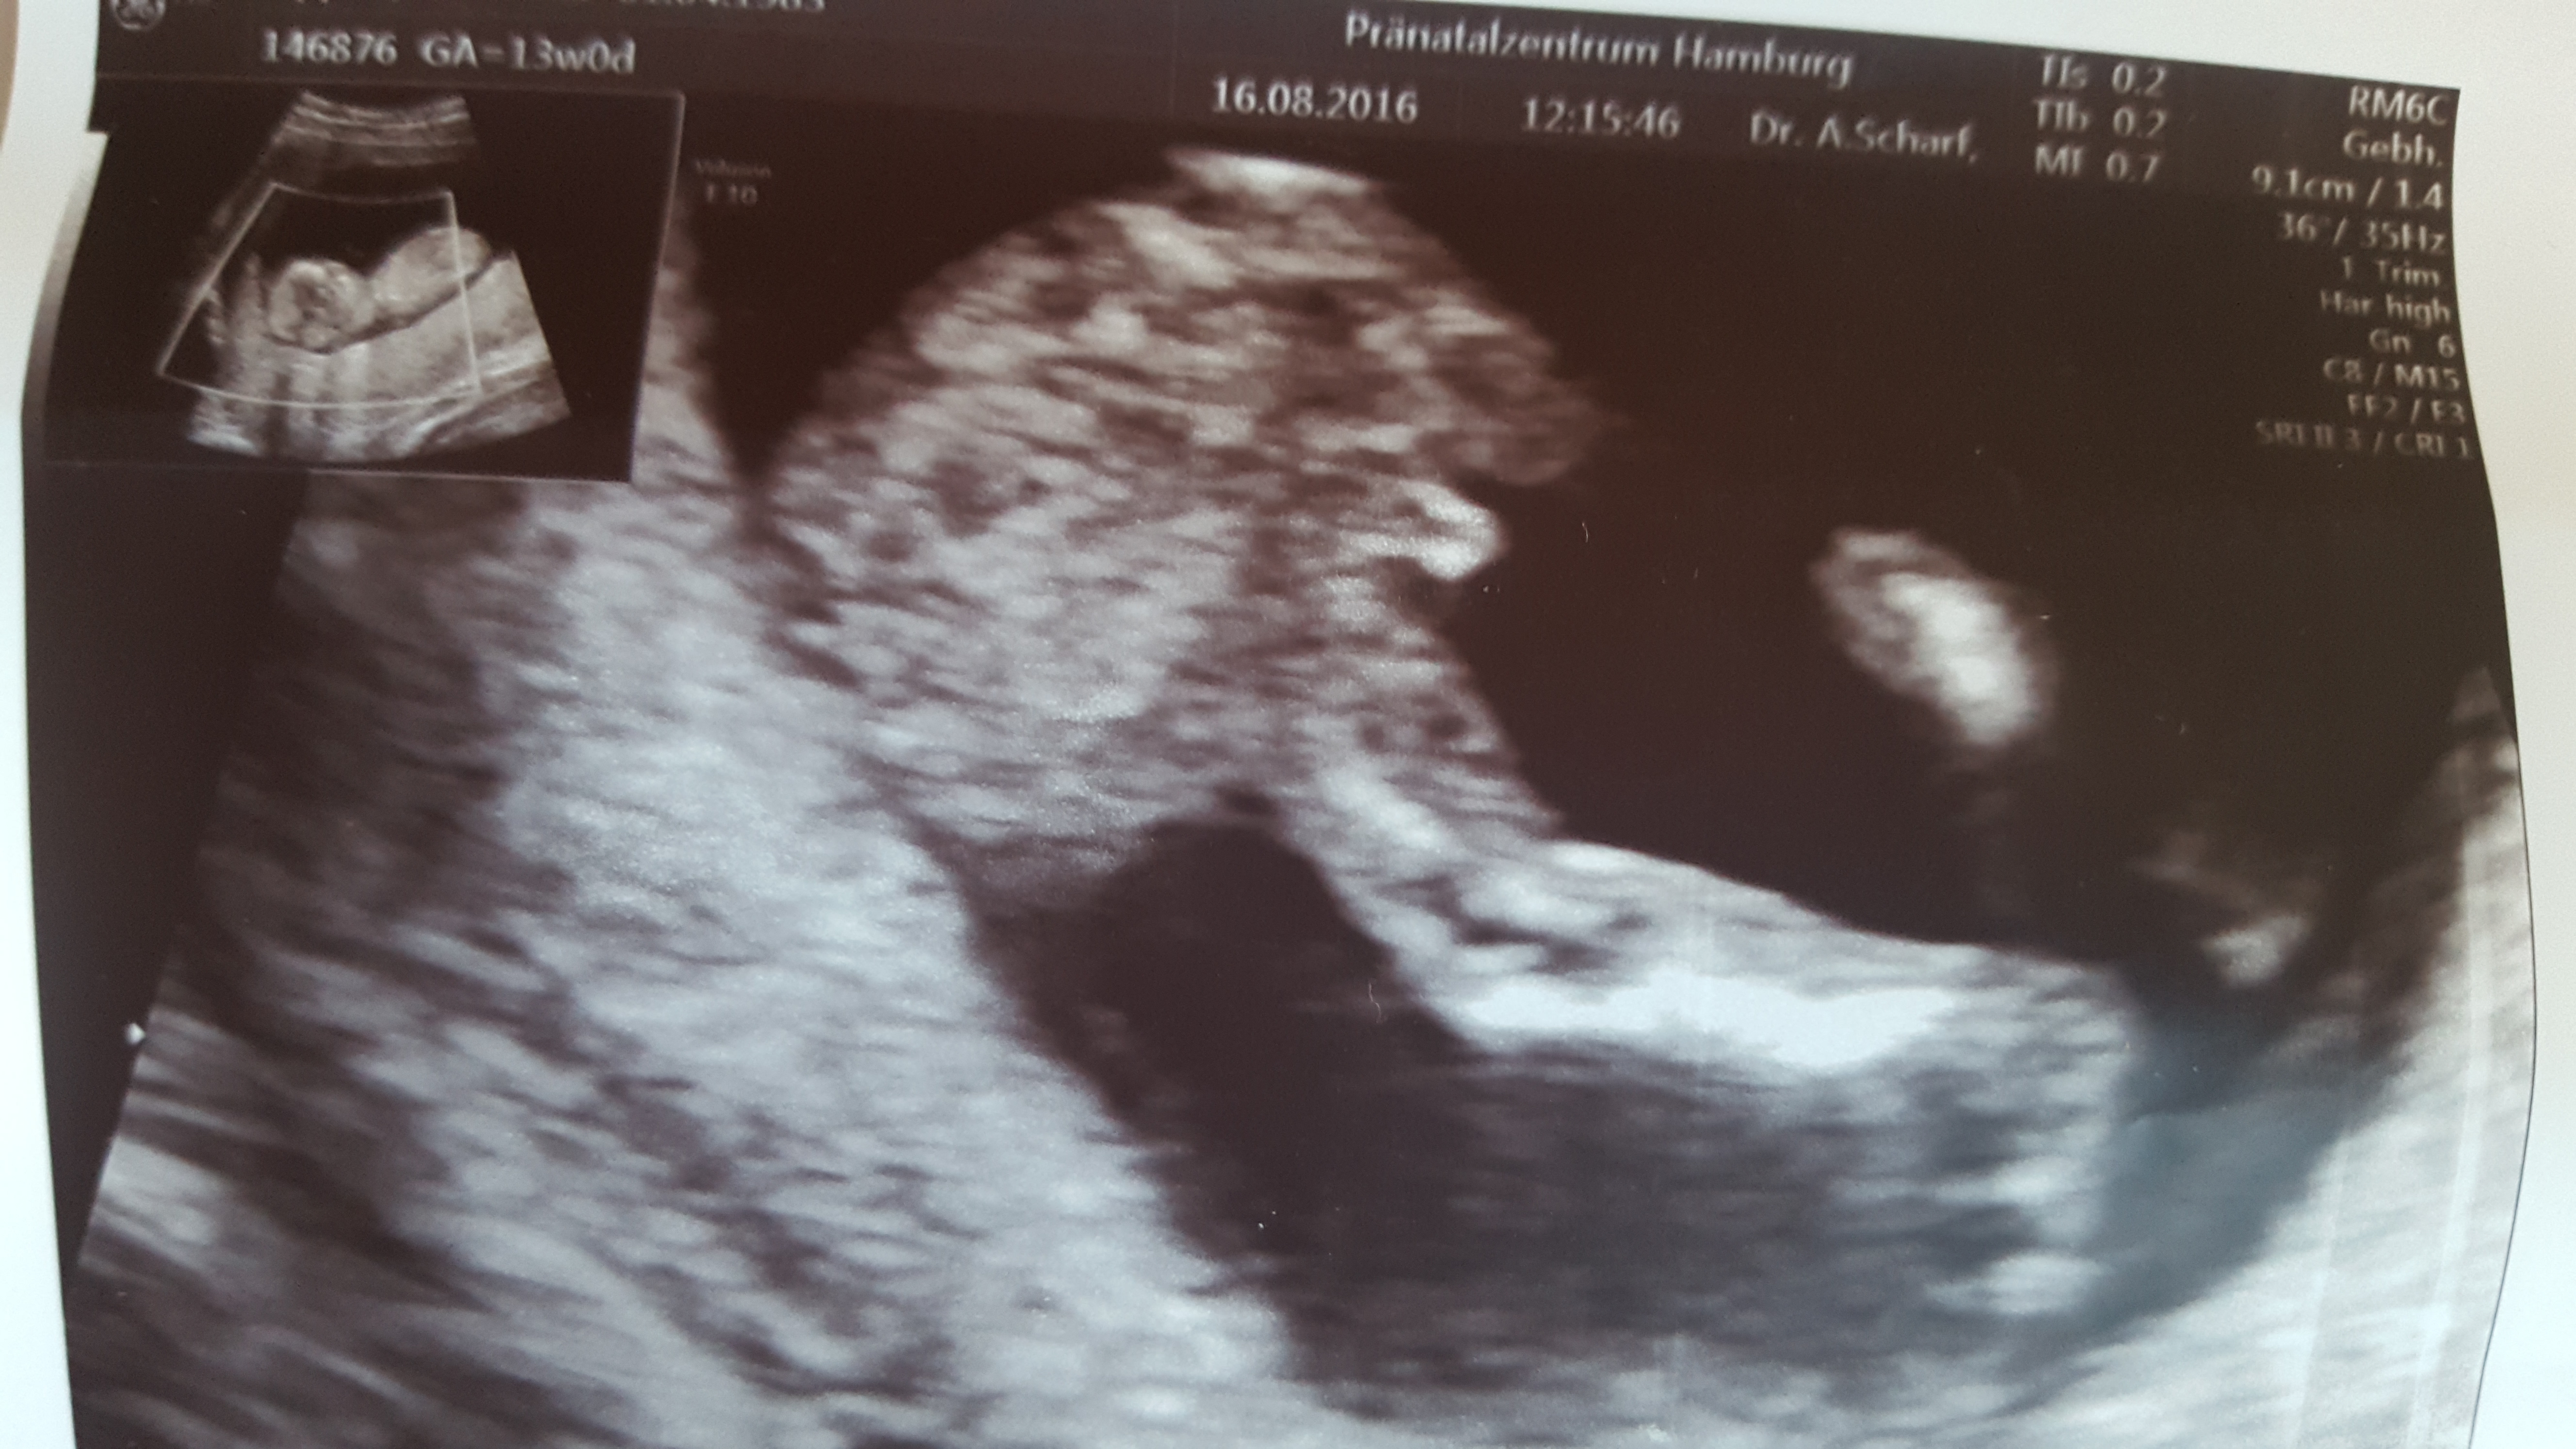

Hey, this was taken 12+6 messuring 13+0, I know potty is early but can such obvious picture still turn into a girl? Any hope? any help? Thank you!!Attachment 32791

Do you have a profile pic to go with this? Both genders can have a protrusion at this stage so lose hope:) All pics you have would be a great help.

I think that is a nub. 11+6 is a little early, but it does appear to be pointing slightly upwards. Your potty I'm not sure of, could be boy or girl. All in all I guess 60% boy. Do you have even more pics? Potty or nub? How many boys do you already have?